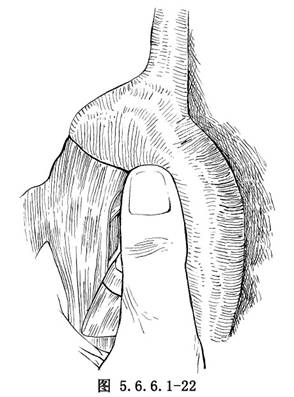

如肿瘤位置较高不能作弓下吻合,应作主动脉弓上吻合,需要将食管继续向上游离。在主动脉弓下缘常有1~2支直接来源于主动脉的食管固有动脉供应食管,要仔细分出,用丝线结扎后切断,不能贸然剪断,否则将造成危险的大出血(图5.6.6.1-21)。一旦固有动脉被损伤,切记不可用止血钳乱夹,术者可用右手示指尖按压出血处(图5.6.6.1-22)。然后用无损伤针及2/0号涤纶线携带一个1cm×1.5cm大的涤纶补片,由按压出血处的示指端右缘进针,由指端左缘出针,用缝线另一端的针由距离前一针0.6cm处的下方再缝一针(图5.6.6.1-23)。两根针再次穿过另一块补片(图5.6.6.1-24)。抽出按压出血处的手指,结扎涤纶线(图5.6.6.1-25)。每个缝线打结6次,如仍有小渗血可补缝数针。正确处理食管在主动脉弓下的固有动脉的方法为由主动脉弓下缘仔细解剖,找出血管后结扎,或切开主动脉弓上缘的纵隔胸膜,用手指由主动脉弓后方、食管前壁与主动脉弓之间轻轻向下外方向顶,即可将固有动脉由弓下显露。如固有动脉位置较深,可用手指尖端由主动脉下方,食管前壁与主动脉弓之间轻轻向上顶,即可将固有动脉由弓上显露(图5.6.6.1-26)。将固有动脉处理完后,即可将已在贲门处切断的食管由主动脉后方提至弓前方作吻合(图5.6.6.1-27)。